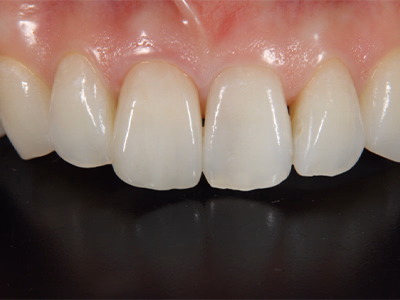

前歯のセラミックス

治療前後写真

治療前

治療後

年齢・性別

50歳・女性

来院理由

前歯の変色・審美障害

治療内容

全体ホワイトニング→失活歯(#11)を再根管治療→#11フルセラミックス修復

#21はレジン充填

治療期間

約3ヶ月

費用

- ホワイトニング 88,000円

- 感染根管治療 121,000円

- セラミック 170,500円

- コンポジットレジン 33,000円

リスク・副作用

歯肉退縮で境目が見える可能性

過度な咬合力でセラミックのチッピング

医院コメント

生物学的安定性を確保した上でセラミックを接着し、色・透明感を自然に調和。